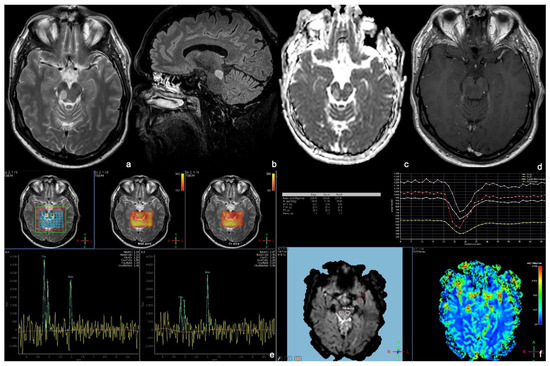

3.2. Enhancing Malignant Gliomas (EMGs)

3.3. Focal Tectal Gliomas (FTGs)